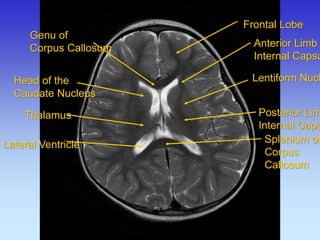

Genu of

Corpus Callosum

Head of the Caudate Nucleus

Thalamus

Lateral Ventricle

Frontal Lobe

Anterior Limb

Internal Capsule

Lentiform Nucleus

Posterior Limb

Splenium of Corpus Callosum